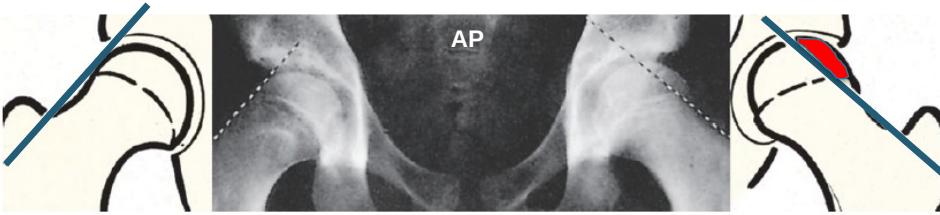

Imaging:

- Required views: AP and Frog lateral pelvis

- Key finding: Slippage of femoral epiphysis

Radiographic Examples:

Comparative views showing slipped vs. normal hip:

(Source: Apley’s System of Orthopedics and Fractures)

X-ray Diagnosis:

| View | Slipped Hip | Normal Hip |

|---|---|---|

| AP |  | - |

| Frog Lateral |  | - |